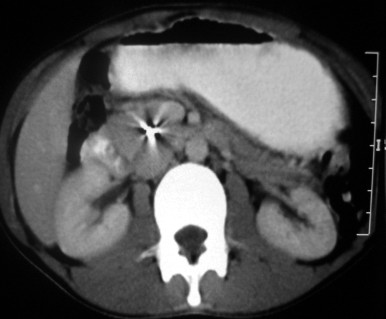

His physical examination and routine blood test, including hemogram, renal function, liver function, serum amylase and lipase were normal. Abdominal computerized tomography (CT) scanogram revealed radio-opaque foreign body at the level of 2nd lumbar vertebra simulating a needle (Figure 1). Contrast enhanced computerized tomography scan showed a thin radio opaque (2,300 HU) linear structure of 6.4 cm embedded within head of pancreas (Figure 2).Patient was planned for laparotomy .Duodenum was kocherized and lesser sac opened. Pancreatic head was firm in consistency, needle could not be palpated, intraoperative sonography was used to localize the foreign body in the head of pancreas. Local resection of needle bearing part of head pancreas preserving duodenum Roux-en-Y pancreaticojejunostomy was done (Figures 3 and 4). Postoperative period was uneventful and patient was discharged on day 7 on satisfactory condition.

Figure 2. CECT showing radio-opaque foreign body in pancreatic head. |